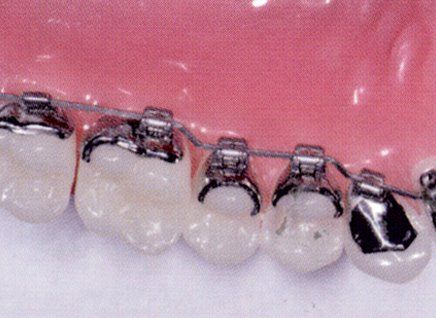

L'ortodonzia dell'adulto è solo ortodontica pura con solo spostamento dei denti, con sistema multi braket estetico trasparente oppure ortodonzia linguale, oppure con mascherine trasparenti (invisalign)

Ci sono vari metodi ortodontici per riuscire a raggiungere un bel sorriso, dall'ortodonzia multi-brackets metallica o trasparente

alla tecnica linguale agli allineatori trasparenti, quest'ultimi nell'ultimo periodo vengono molto richiesti.